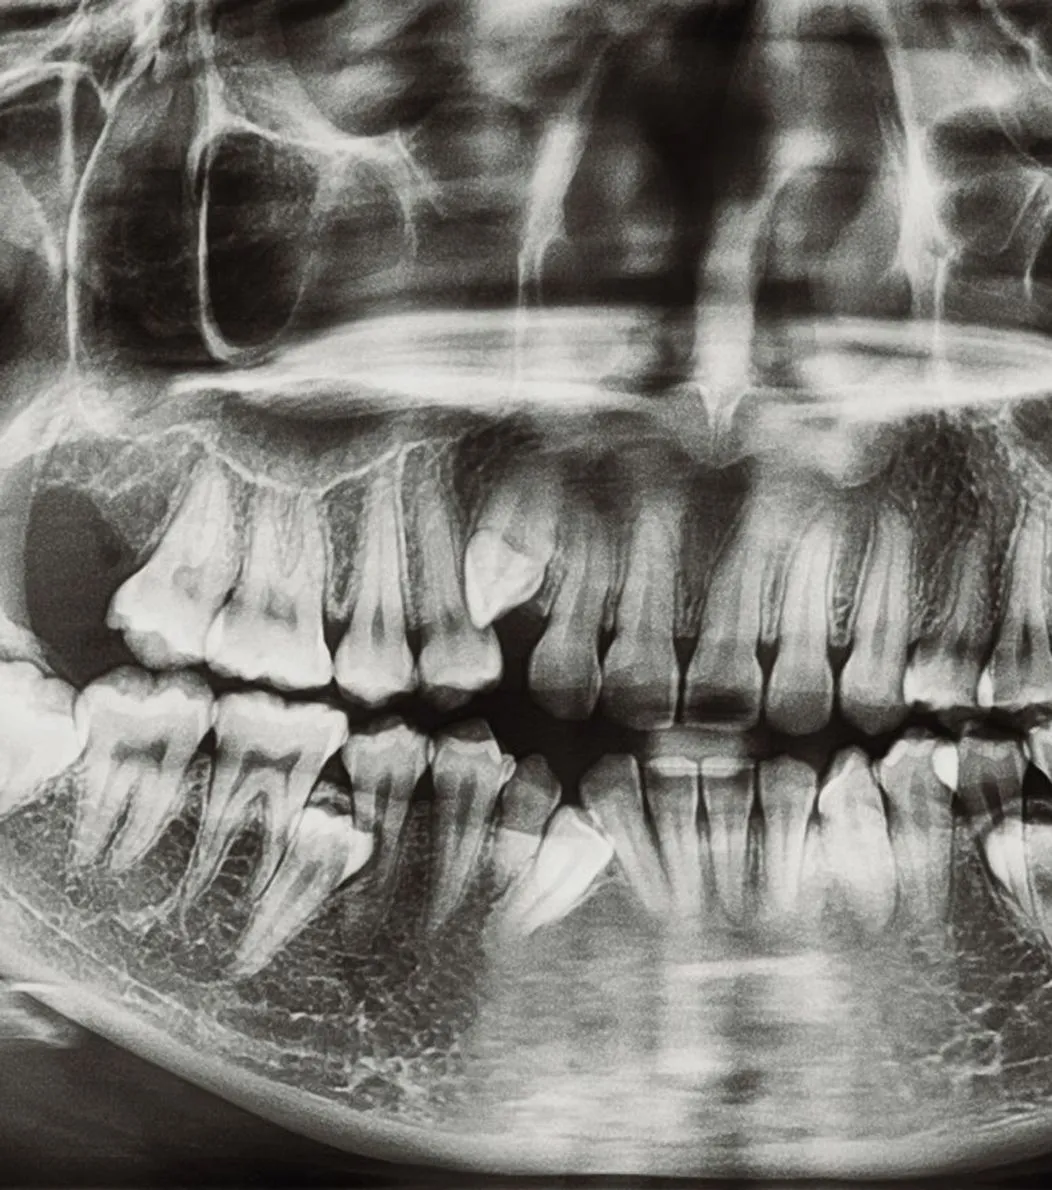

Dental implants are a long-term solution that feels and functions like a natural tooth. The implant is placed in the jawbone where it bonds with the bone, creating a secure foundation for a custom crown. Implants help maintain bone strength, improve chewing ability, and restore the appearance of your smile. With the right care, they can last for many years.